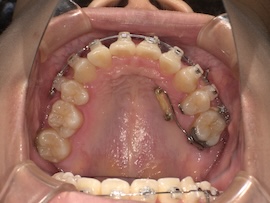

実際に処置をしてもらった直後の写真がこちらです。

まだ麻酔で感覚がないため、唾液が多く見えづらくてすみません。(笑)

意外と近くに埋まっていたそうなので、少し歯茎を切る程度で済んだみたいです。骨は削っていないので腫れもほとんどありません。

その後も歯茎を切った痛みは特別感じることなく、親知らずを引っ張ることに関しても今まで感じた歯の動く痛みと同じくらいでした。ただ全体的な痛みではないため反対側で普段通りの食事はできますし、覚悟していた分全然楽に感じます。(笑)

また、一度だけ歯磨き中に出血してしまって驚きましたが、少し裂けてしまっただけで特に問題ありませんでした。